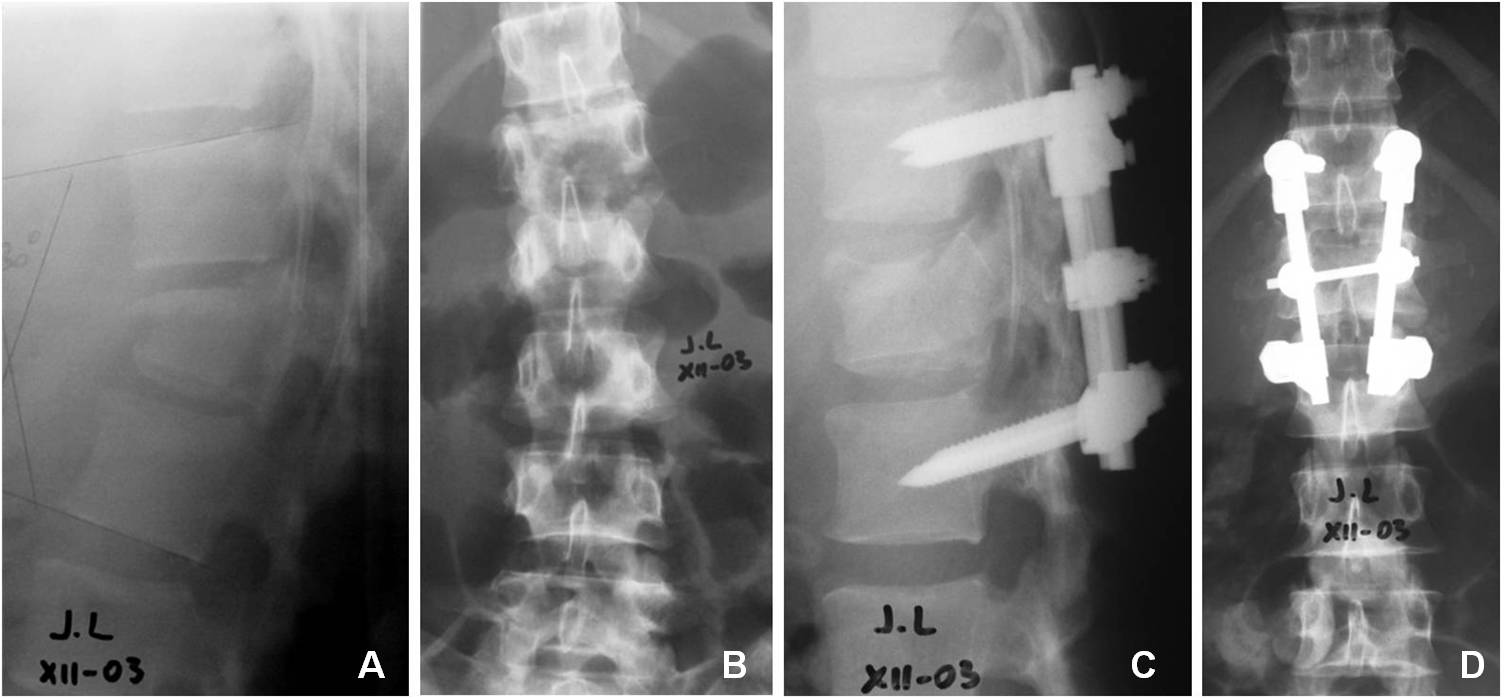

Introducción: El tratamiento quirúrgico de las fracturas toracolumbares es controvertido. La vía de abordaje y la cantidad de niveles de instrumentación son motivo de debate. El objetivo de este estudio fue analizar los resultados radiológicos y clínicos de pacientes con fracturas toracolumbares por estallido y flexión/distracción.MaterialesyMétodos: Estudio retrospectivo de una serie consecutiva de pacientes tratados quirúrgicamente entre 2004 y 2008, con seguimiento >12 meses. Se incluyeron pacientes con instrumentación y artrodesis corta de los niveles adyacentes a la lesión, abordados por vía posterior. Se tomaron en cuenta fracturas de tipo A3 y B de la clasificación AO. Se llevaron a cabo evaluaciones clínica, neurológica y radiológica.Resultados: Se registraron 25 pacientes, 3 se perdieron en el seguimiento y 22 fueron analizados. El promedio de edad fue de 37 años. La causa más frecuente fue caída de altura, seguida de accidente vehicular. El nivel más afectado fue L1. El promedio de cifosis preoperatoria fue de 14º y de 4º en el posoperatorio alejado. En la evaluación clínica, 10 pacientes tuvieron un excelente resultado; 10, bueno y 2, regular. No hubo compromiso neurológico en 21 pacientes.Conclusiones:La instrumentación corta proporciona muy buenos resultados en la mayoría de los pacientes tanto a nivel radiológico como funcional. La selección de los pacientes debe ser estricta, se debe excluir a aquellos con cifosis grave, conminución importante u otro factor que haga pensar en la necesidad de un abordaje anterior. En el seguimiento alejado, no se observa una pérdida significativa de la reducción en la cifosis.Descargas